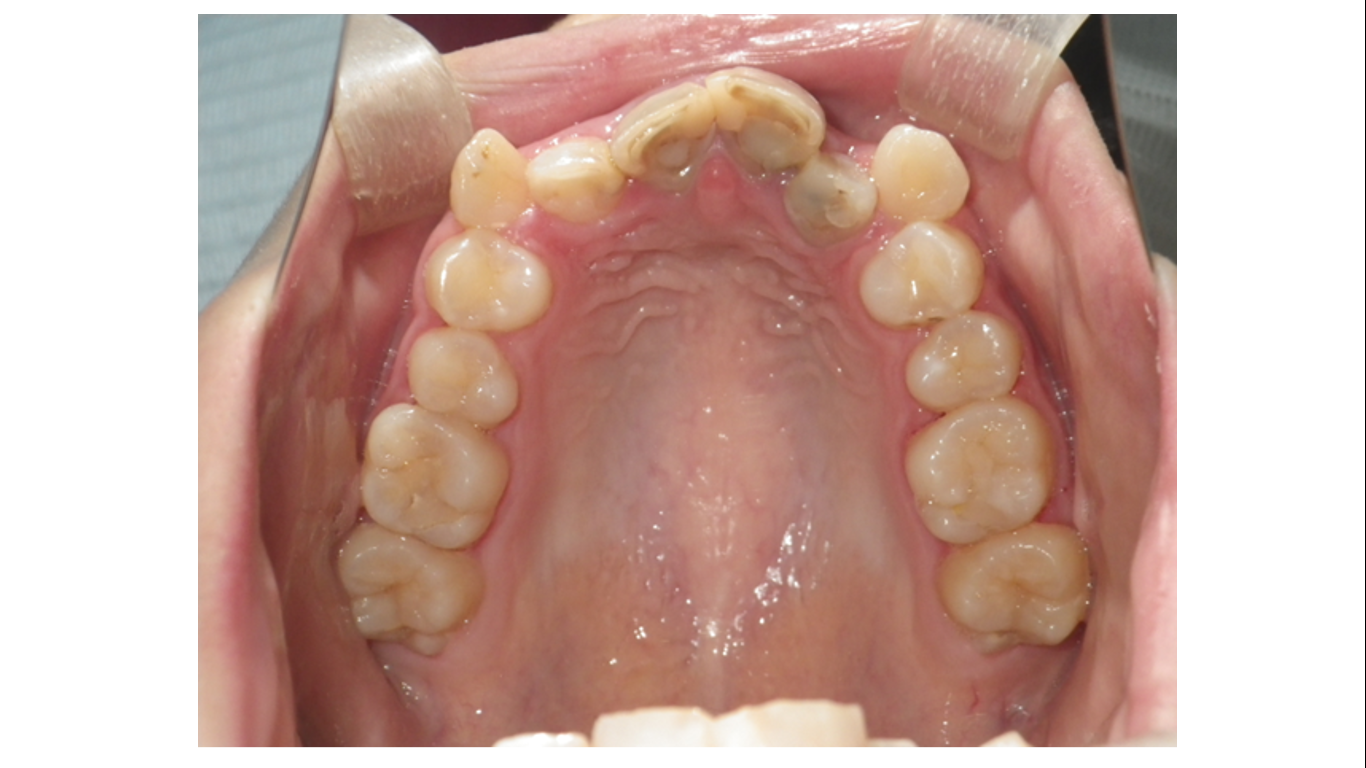

上の写真は術前の口腔内写真です。上顎切歯のレジン充填がお粗末すぎるのでやり直しが必要です。下顎右側側切歯が先天性欠如であると判ります。

初診時の上顎咬合面です。上顎左右1番、上顎右側2番のレジン充填が不良です。上顎の叢生が除去されて後にレジン充填をやり直しました。